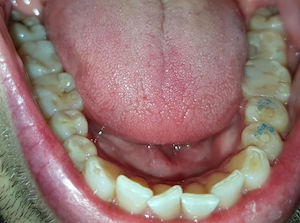

19.1.26: Der -7 wurde beim Pressen stark belastet und hat stark geschmerzt.

Beide apikalen Aufhellungen sind sehr klein.

Ist die Ursache bakteriell oder nur mechanisch?

Die Patientin spürt, dass sie häufig ihre Zähne zusammenpresst. Deswegen hatte sie am 19.1.26

starke Schmerzen links unten.

Am 22.1.26 waren diese verschwunden, dafür schmerzte nachher die Wange links oben.

Bei den oberen Molaren zeigt das Röntgenbild keine Aufhellung.

Ist der -7 entzündet und braucht er eine Wurzelbehandlung?

Stattdessen hab ich ihr eine FOS-Knirscherschiene gemacht. Diese wird zeigen, ob die Beschwerden wieder aufhören.

Die Patientin hat einen Nachtbruxismus und spürt morgens verspannte Wangen. Sie hat nur Kontakt auf den hintersten Molaren und keine Schmerzen. Das reibende Geräusch ist wahrscheinlich eine stabile Diskus-Degeneration und braucht keine Behandlung.